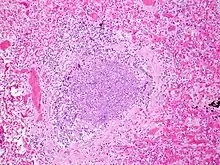

La période d'incubation est de deux à huit jours, puis le virus se multiplie dans la muqueuse nasale (une rhinopharyngite inaugure ainsi fréquemment une bronchiolite). Il gagne ensuite les voies respiratoires inférieures pour atteindre les bronchioles où il se multiplie, au sein des cellules épithéliales.

Le tableau clinique est dû à une obstruction des voies aériennes, d'une part causée par un bouchon muqueux obstruant la lumière, d'autre part due à une inflammation de la paroi bronchique. Le bouchon muqueux est créé par l'accumulation de cellules mortes et de sécrétions muqueuses. L'obstruction n'est que peu liée au spasme bronchique, les muscles lisses étant encore peu développés à cet âge.